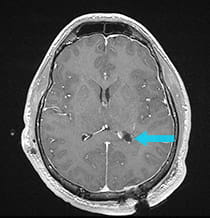

Pre-surgical scan shows a intraventricular tumor. Post-surgical scan shows the ventricle is visible on the scan as a dark space.

After successful surgery, the ventricle is visible on the scan as a dark space.

The post-surgical MRI shows complete removal of the tumor. The patient's confusion and headaches resolved, with just minor visual difficulty remaining.